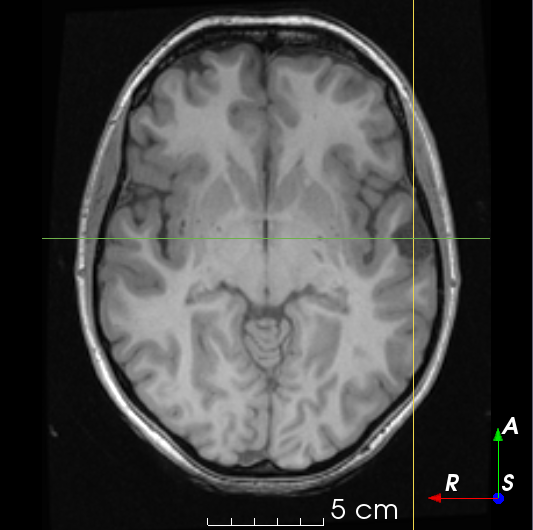

2.2 Dataset Description

T1𝑇1T1-weighted MR images were collected from publicly available datasets Information eXtraction from Images (IXI) (566), Alzheimer’s Disease Neuroimaging Initiative (ADNI) (467), and Open Access Series of Imaging Studies (OASIS) (780), for a total of 1813 images. EPISURG was obtained from patients with refractory focal epilepsy who underwent resective surgery at the National Hospital for Neurology and Neurosurgery (NHNN), London, United Kingdom. This was an analysis of anonymized data that had been previously acquired as a part of clinical care, so individual patient consent was not required. In total there were 431 patients with postoperative T1subscript𝑇1T_{1}-weighted MR images, 269 of which had a corresponding preoperative MR image. All images were registered to a common template space using NiftyReg [17].

Three human raters annotated a subset of the postoperative images in EPISURG. Rater A segmented the resection cavity in 133 images. These annotations were used to test the models. This set was randomly split into 10 subsets, where the distribution of resection types (e.g. temporal, frontal, etc.) in each subset is similar. To quantify inter-rater variability, Rater B annotated subsets 1 and 2 (34 images), and Rater C annotated subsets 1 and 3 (33 images).